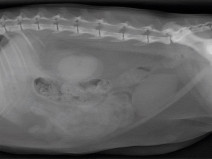

• Travaux dirigés de radiographie abdominale

Le GEIM vous propose une séance de travaux dirigés de radiographies sur l'abdomen. Tous les aspects sont abordés sous la forme de TD de lecture de radiographies numériques.

Le 4 octobre 2022

- Classe virtuelle ()

Imagerie Médicale

G.E.I.M.

1275